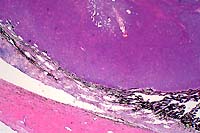

- Case 12-3. Eye. As described below.

- Gross Pathology: An irregularly shaped, pale tan mass

measuring approximately 0.75 cm in diameter was present within

the globe and extended caudally from the iris.

- Contributor's Diagnosis and Comments: Eye: Iridociliary

adenocarcinoma.

- A partially encapsulated, highly cellular mass consisting

of cuboidal to polygonal cells arranged in loose cords, packets,

and occasional rosettes is adherent to the posterior aspect of

the iris and to the ciliary body. The neoplasm infiltrates the

base of the iris and extends into the filtration angle. Irregularly

shaped, dilated channels are present in some areas, and the mass

is supported by a fine fibrovascular stroma. Cells within the

mass have large, round to oval, occasionally indented nuclei,

1-2 nucleoli, finely stippled chromatin, small to moderate amount

of foamy, eosinophilic cytoplasm, and variably-distinct to indistinct

cell margins. A few cells have large, irregularly shaped nuclei,

and the mitotic rate varies from 0-3 per high-powered field.

Some scleral vessels adjacent to the neoplasm contain thrombi

and seemingly have "infiltrates" of cells (may not

be visible in all sections); the cells are dissimilar to those

within the neoplasm and may, in fact, represent a reaction to

thrombosis or other negative vascular events.

2x

obj

- Case 12-3. Eye. A monomorphic mass replaces the iris.

40x

- Case 12-3. Ocular tumor. Sheets of pleomorphic polygonal

cells occasionally palisade around a central lumen (pseudorosette

formation).

- AFIP Diagnosis: Eye: Ciliary body adenocarcinoma,

Domestic Longhair, feline.

- Conference Note: This neoplasm was studied in consultation

with the Department of Ophthalmic Pathology. Conference participants

agreed with the contributor's diagnosis. An expansile, infiltrative,

densely cellular neoplasm has effaced the ciliary body and is

composed of polygonal cells arranged in packets, nests, tubular

structures, and pseudorosettes, supported by a fine fibrovascular

stroma. Neoplastic cells have significant atypia, with occasional

bizarre cells. The mitotic rate is high. Scattered within the

tumor are entrapped melanophages which contain moderate amounts

of brown-black granular to globular pigment.